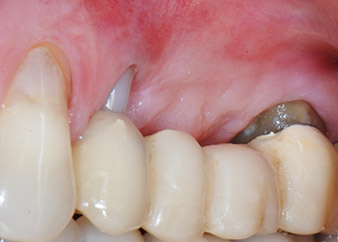

A 58-year-old female patient complained of pain and increased mobility of her bridge abutment tooth 24. Periodontal inflammation was present with pocket depths of 7 mm mesiobuccally and more than 12 mm distally, as well as third-degree furcation involvement. Moreover, the radiograph revealed an extensive periodontal lesion around the apical region of the (alio loco) endodontically pretreated tooth 24 (Fig. 1).

One month later, on the day of surgery, pain and inflammation at tooth 24 were minimal, but mobility of Miller class 2 was still present. After opening the flaps and cleaning the periapical and peri radicular infected tissue, the extent of the bone defect became obvious (Figs. 2 and 3).

At the buccal root, all vestibular and distal bone was missing. Attachment was essentially restricted to the palatal root, underlining the preliminary poor prognosis. Tooth 27 also showed a reduced horizontal attachment and a minimal apical rarefaction (cf. Fig. 1) without clinical symptoms.